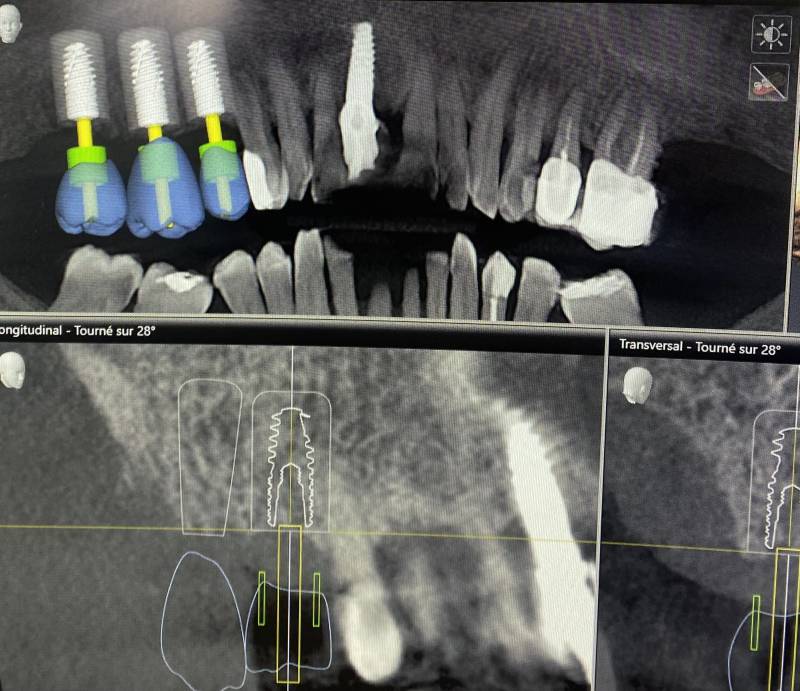

L'utilisation de l'imagerie 3D est quant à elle indiquée pour visualiser les bases osseuses pour la planification de chirurgie implantaire, de greffe osseuse, la détection des limites périphériques d'un kyste, la localisation de dents incluses (canine incluse au palais ou dent de sagesse), la visualisation de l'anatomie canalaire pour les traitements endodontiques (dévitalisation).